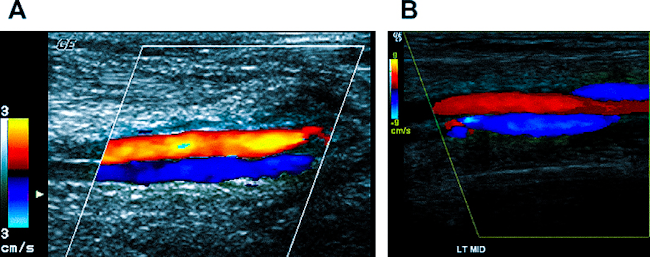

Фото: УЗДС артерий и вен - простейший и быстрый способ оценки кровотока в конечности, но - довольно субъективный способ, важна экспертная оценка.